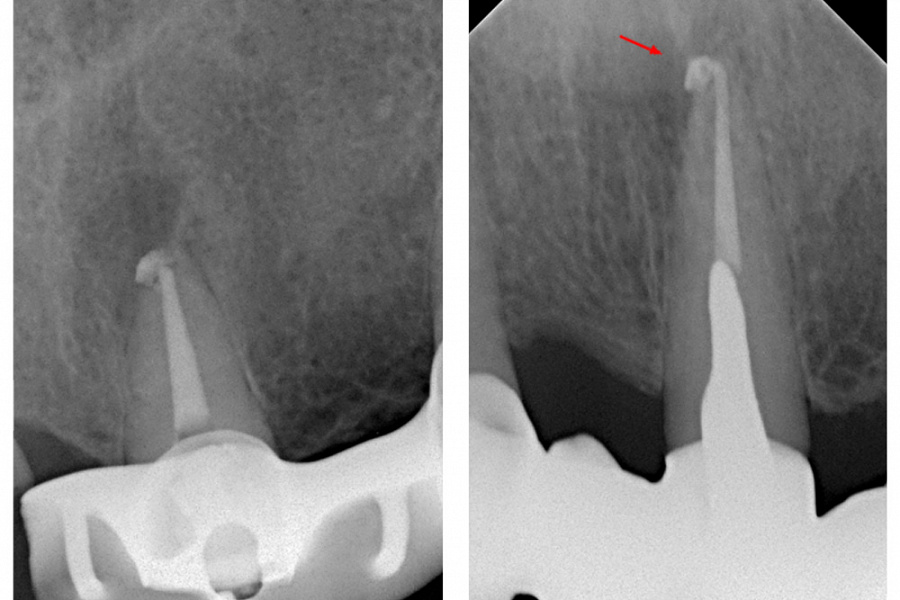

На контрольном снимке через 12 месяцев после лечения отмечается репарация тканей в области верхушки 21 зуба (снимок 4). Жалобы отсутствуют.